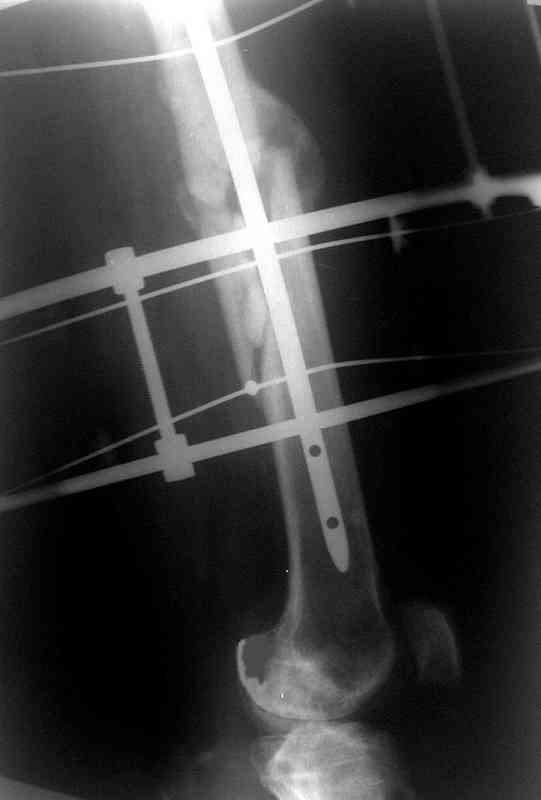

Больной А., 28 лет, поступил в НИИ им. Н.В. Склифосовского 22.12.99 после падения на улице. Жалобы на боли в области левого тазобедренного сустава и левом бедре. Из анамнеза следовало, что 20.06 во время прыжка с парашютом у него возник закрытый оскольчатый перелом средней трети левой бедренной кости со смещением отломков, по поводу чего в одной из ЦРБ Московской области через 3 дня после травмы был произведен открытый интрамедуллярный остеосинтез штифтом типа Кюнчера.

Послеоперационное течение было гладким. Больной ходил при помощи костылей с дозированной нагрузкой на оперированную конечность.При осмотре в НИИ им. Н.В. Склифосовского через 6 месяцев после травмы:

левое бедро и левый коленный сустав несколько увеличены в объеме, отечны, пальпаторно определяется болезненность в средней трети бедра;

по его наружной поверхности послеоперационный рубец - рана зажила первичным натяжением. При измерении длины бедер обнаружено укорочение левого бедра на 4,5 см. На рентгенограммах этого бедра: ось конечности правильная, отмечается захождение основных костных фрагментов по длине, проксимальный конец штифта выступает слишком медиально и высоко относительно большого вертела, периостальная мозоль незначительна.22.12 - через 6 месяцев после операции, произведенной в ЦРБ, нами по поводу замедленно консолидирующего перелома левой бедренной кости с ее абсолютным укорочением под наркозом произведена операция: удаление штифта, закрытый блокирующий интрамедуллярный остеосинтез перелома левого бедра штифтом без рассверливания (UFN) длиной 40 см, диаметром 10 мм с блокированием только проксимальных отверстий (динамический остеосинтез). Наложен аппарат Илизарова на 4 полукольцах с целью удлинения укороченного бедра. Послеоперационное течение без особенностей. Ежедневно осуществляли дистракцию отломков на 1 мм. Через 3 недели после операции больной выпи-сан на амбулаторное лечение с продолжением дистракции отломков. В течение 1,5

месяцев дистракции укорочение левого бедра удалось полностью устранить. 22.02.00, т.е. через 2 месяца после повторного остеосинтеза, больному произведено дистальное блокирование штифта двумя винтами и демонтирован аппарат Илизарова. В течение 2 недель после операции больной ходил с помощью костылей, потом 2 недели с тростью. Опороспособность и функция оперированной конечности полностью восстановились через 4 недели после операции.

Фиксаторы удалены через 12 месяцев после операции, выполненной по поводу замедленной консолидации перелома бедра с его укорочением.